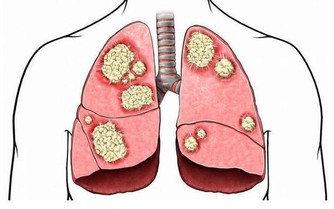

肝臟有不少“天敵”,首推肝炎病毒。換言之,肝炎病毒乃是肝臟健康的首要敵人,它們常將罹患者拖入肝炎——肝硬化——肝癌的死亡之路。目前科學家已發現甲、乙、丙、丁、戊、庚等6種型號肝炎病毒,其中尤以乙、丙、庚等型號最為凶險。最有效的手段是接種疫苗,如甲型、乙型肝炎疫苗。以甲型肝炎為例,疫苗應用近十年,受益者接近1億人,致使該型肝炎的感染率以每年平均22%的速度下降,估計20年後可消滅此病。

首先倒霉的便是肝臟,因為酒精本身就含有毒性,足以傷害肝臟,脂肪肝是最早出現的徵兆,

只需豪飲幾天便可以形成,接著導致“纖維化”,再變成酒精性肝病,隨後情況就更糟了,

最終發展到不可逆的“肝硬化”。